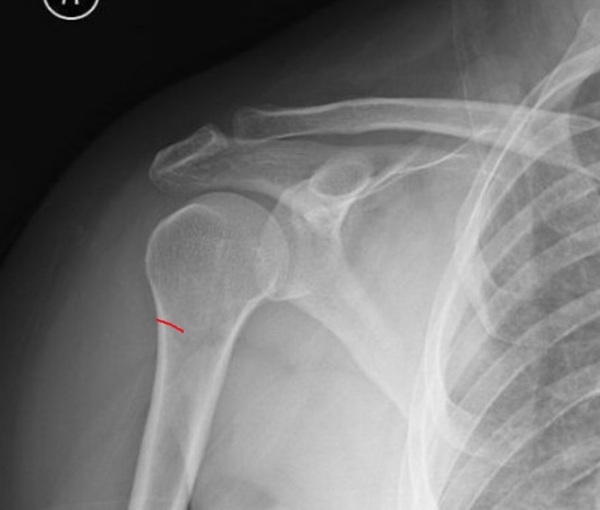

P.S. Кому интересно, то вот то место, которое меня угораздило сломать (шейка плеча или что-то такое, сейчас уже не помню). Снимок не мой. Нашёл в интернете. Свой рентген потерял при переезде.